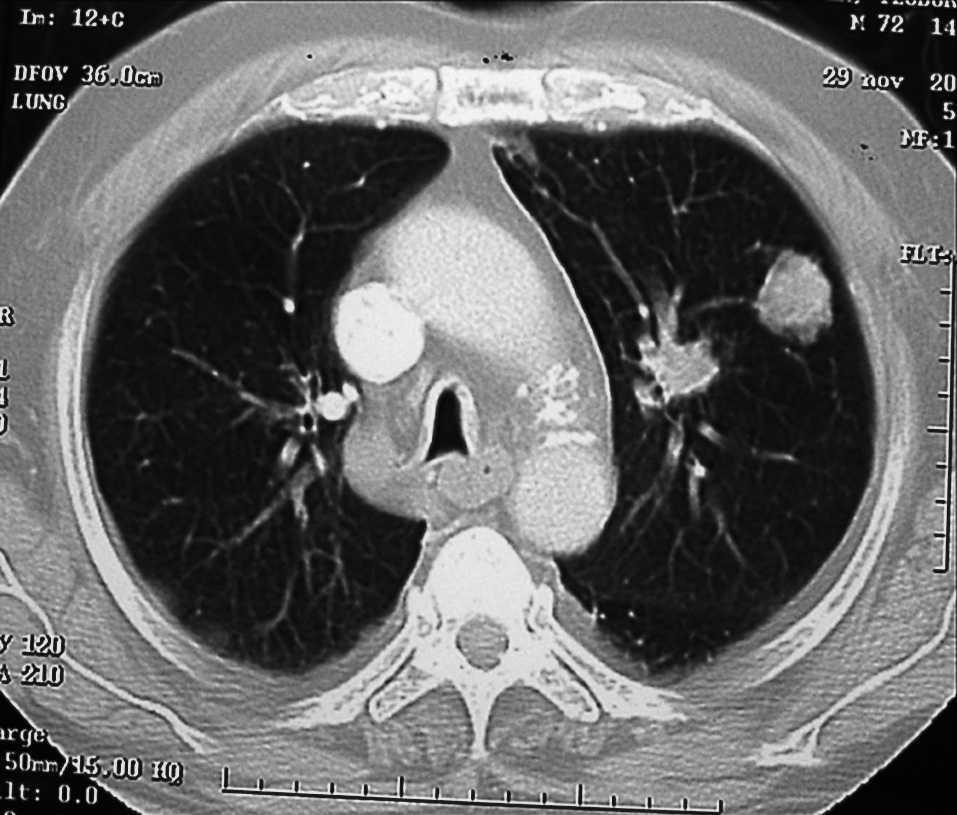

Se le practicó una tomografía computarizada (TC) con contraste intravenoso en la que se descubrieron pequeñas adenopatías menores de 1 cm en la región retrocava y la ventana aortopulmonar, y en el lóbulo superior izquierdo (LSI), un nódulo de 3 cm de contornos abollonados y espiculados que no contactaba con la pleura visceral. En la base del pulmón derecho había un nódulo menor de 1 cm sin derrame pleural acompañante y un hemiabdomen superior normal (fig. 1).

Fig. 1. Corte axial de tomografía computarizada con nódulo pulmonar en lóbulo superior del pulmón izquierdo.